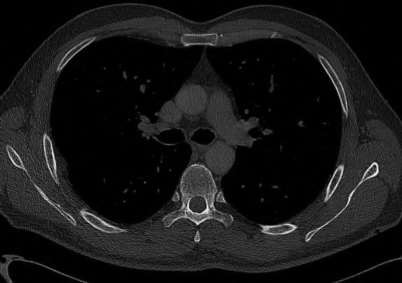

A 35-year-old woman reports wrist pain after a fall onto an outstretched hand. On exam, she has focal tenderness over the wrist snuffbox. A radiograph and CT image are shown in Figures A and B. What is the proper treatment of her injury?